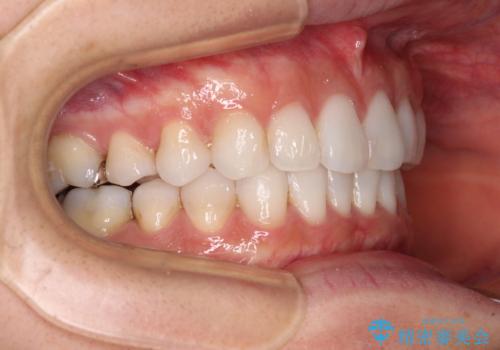

- 前歯のデコボコを気にして来院された患者様です。

海外に留学をされており、卒業後はしばらく日本にいるものの、再び就職のため出国するとのことでした。

定期的に日本に戻ってくる予定であるため、来院頻度の少ないインビザラインにて矯正治療を行うこととしました。

歯列不正が軽度であり、インビザラインの装着時間を遵守してくださったため、日本と海外を行き来しながらも2年弱でしっかりと仕上げることができました。